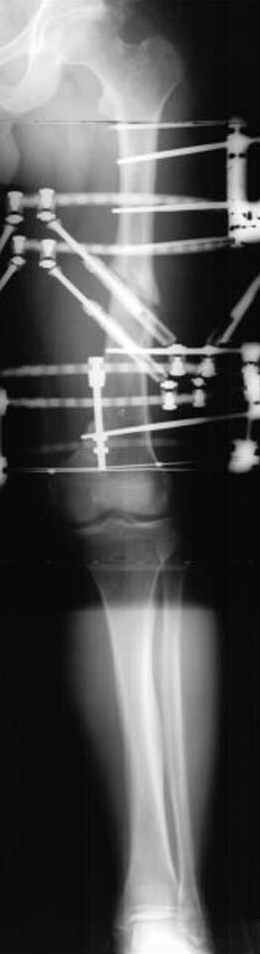

Отправитель: Alexander Chelnokov 23 Ноябрь 2004, 02:31

Если, например, доводится лечить больных с псевдартрозами шейки бедра, то надобность есть, и приходится. См. приложение.

Отправитель: Djoldas Kuldjanov 23 Ноябрь 2004, 18:21

пластическая модель; и коррекция бедра аппаратом Илизарова.

Имею другие снимки тоже, получится как отчет о моей работе.

Отправитель: Evgueny Tschekashkin 23 Ноябрь 2004, 21:28

Почему не замена гвоздя с рассверливанием, а аппарат?

• Re: Hip joint

Попробую угадать - была инфекция?

Отправитель: Evgueny Tschekashkin 24 Ноябрь 2004, 21:09

хотя даже если бы и инфекция , то nail exchange с рассверливанием канала - вариант дебрайдмента) Я думаю, что последовательность развития событий:

Узкий к-м канал - тонкий гвоздь- усталостный перелом дистальных винтов - развитие нестабильности и как ее результат остеолиз вокруг гвоздя - деформация анатомической оси бедра. Похоже, что я понял почему аппарат, а не новый гвоздь:-)

Отправитель: Alexander Chelnokov 24 Ноябрь 2004, 21:11

ET> хотя даже если бы и инфекция , то nail exchange с рассверливанием канала -

ET> вариант дебрайдмента)

Да, но если, скажем, течет из инфицированных каналов запирающих винтов, да инфекция в дистальном метафизе бедра - устанешь сверлить.

Аппарат в таком случае средство из серии "тише едешь - дальше будешь".

ET> Я думаю, что последовательность развития событий:

[...]

ET> деформация анатомической оси бедра.

Да, наверно. Но если ничего другого нету, ту небольшую деформацию можно было устранить дистрактором одномоментно ввести другой гвоздь.

ET> Похоже, что я понял почему аппарат, а не новый гвоздь:-)

Отправитель: Evgueny Tschekashkin 24 Ноябрь 2004, 21:13

> Да, но если, скажем, течет из инфицированных каналов запирающих винтов, да инфекция в дистальном метафизе бедра - устанешь сверлить.

ЕТ-Теоретически это возможно, а практически трудно представить - все-таки уровень медицинского сервиса высок, поэтому вряд ли инфекционное воспаление может зайти так далеко.....

> Тогда делись догадкой скорей!

ЕТ - Изначально костно-мозговой канал бедра был узкий, дальнейшее его рассверливание ещё больше скомпрометирует прочность бедра( латеральный кортекс дистального отломка уже истончен), приведет к дефекту наружной стенки - хотя это только мои догадки - хотелось бы знать мнение Джолдаса о выбранной тактике.